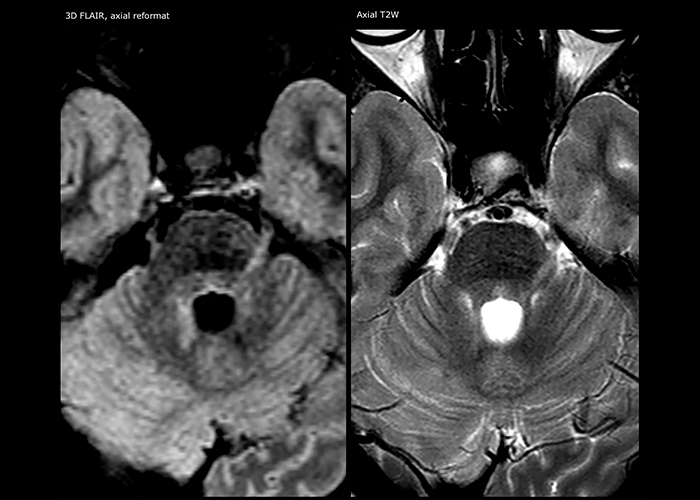

“For MS imaging in the spine, the basic examination includes a sagittal T2 and a post-contrast sagittal T1-weighted sequence in the whole spine. These are done in two stacks and using thin slices, for example 2 mm, without gap. As in the brain, the T2-weighted sequence visualizes the overall lesion load and helps determine if lesions are old or new. The post-contrast T1- weighted sequence helps in assessing if a lesion is new. We will sometimes add a T1 inversion recovery sequence, which has very good sensitivity, if we don’t find any lesions on T2,” Dr. Savatovsky says. “Additionally, if there is contrast enhancement outside the spine, it’s usually not MS but another kind of inflammation.”